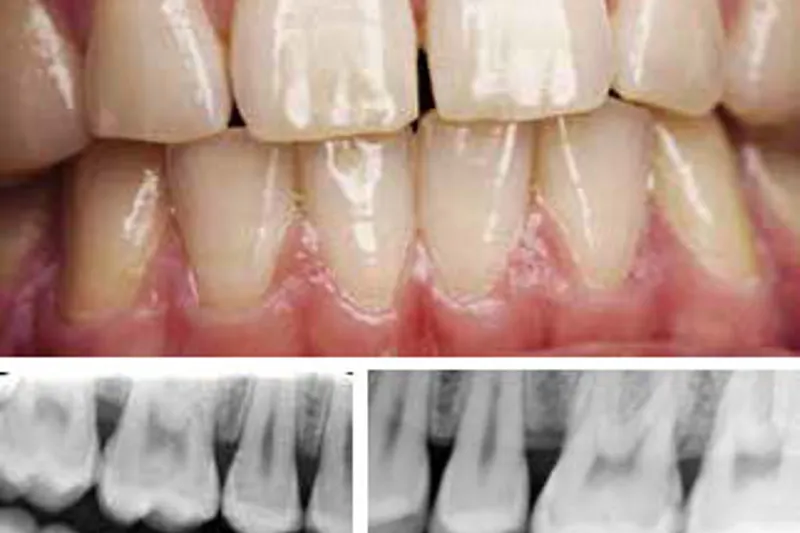

Klassifikationen af parodontale sygdomme er blevet reorganiseret efter et omfattende arbejde i ekspertgrupper efterfulgt af en international workshop arrangeret af American Academy of Periodontology og European Federation of Periodontology i 2017. På workshoppen enedes et internationalt ekspertpanel med repræsentanter fra lande over hele verden om definitionerne, som ud over en beskrivelse af parodontitis også indeholdt beskrivelser af det intakte parodontium, parodontal sundhed, biofilminduceret gingivitis og ikke-biofilminduceret gingival sygdom. Denne artikel fokuserer på parodontitis. Parodontitis er en tilstand med klinisk fæstetab (clinical attachment loss, CAL) på mindst 1 mm interdentalt på mindst to tænder, som ikke er nabotænder, eller CAL på mindst 3 mm facialt/lingvalt på mindst to tænder. Parodontitis inddeles yderligere i fire stadier (I-IV) efter sygdommens alvorlighed og i tre grader (A, B, C) efter progressionshastighed og risikofaktorer. Endvidere skal sygdommens udbredelse og fordeling i tandsættet angives. Vi beskriver her, hvordan den nye parodontitisklassifikation kan anvendes i daglig klinisk praksis, og hvordan implementering af den nye klassifikation kan gavne patienter og klinikere og give et bud på, hvor stort problemet er, dvs. prævalensen af fremskreden parodontitis. Artiklen illustrerer endvidere de nye begreber, stadier og grader ved hjælp af repræsentative patienttilfælde.

The classification of periodontal diseases has been re-organised after extensive work in expert groups followed by an international workshop arranged by the American Academy Periodontology and the European Federation of Periodontology in 2017. The international expert panel at the workshop representing countries from around the world has agreed on the definitions, which in addition to a description of periodontitis include descriptions on the intact periodontium, periodontal health, biofilm-induced gingivitis, and non-biofilm-induced gingival disease. The present article focuses on periodontitis. Periodontitis is a condition with interdental clinical attachment loss (CAL) of at least 1 mm on at least two non-neighbouring teeth or a buccal/lingual CAL of at least 3 mm on at least two teeth. According to severity periodontitis is further subdivided in four stages (I – IV), and three grades (A, B, C) according to rate of progression and risk factors. Furthermore, the extent and distribution of the disease must be stated. Here we describe how the new classification on periodontitis applies to every-day clinical practice, how can patients and the clinical profession benefit from implementation of the new classification, and what is the magnitude of the problem, i.e. the prevalence of severe periodontitis? The article also presents representative cases to illustrate the new concept of staging and grading.